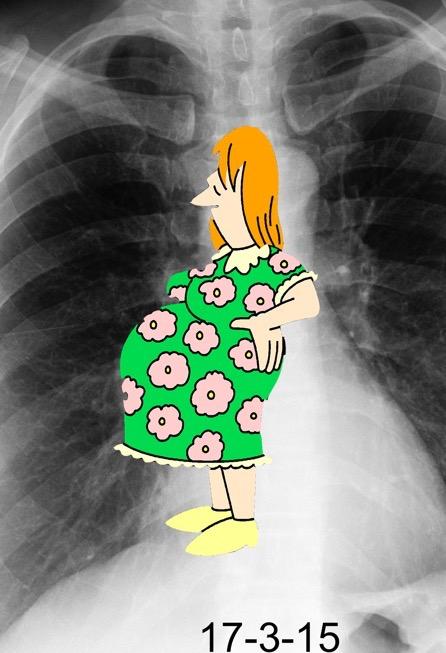

147. TORACO-ABDOMINAL, SIGNO

¡El vestido de embarazo! Felson. B

Signo definitivo de la situación extrapleural:

de:

Felson B. Localization of intrathoracic lesions. In: Chest roentgenology. Phila-delphia, PA: Saunders, 1973.